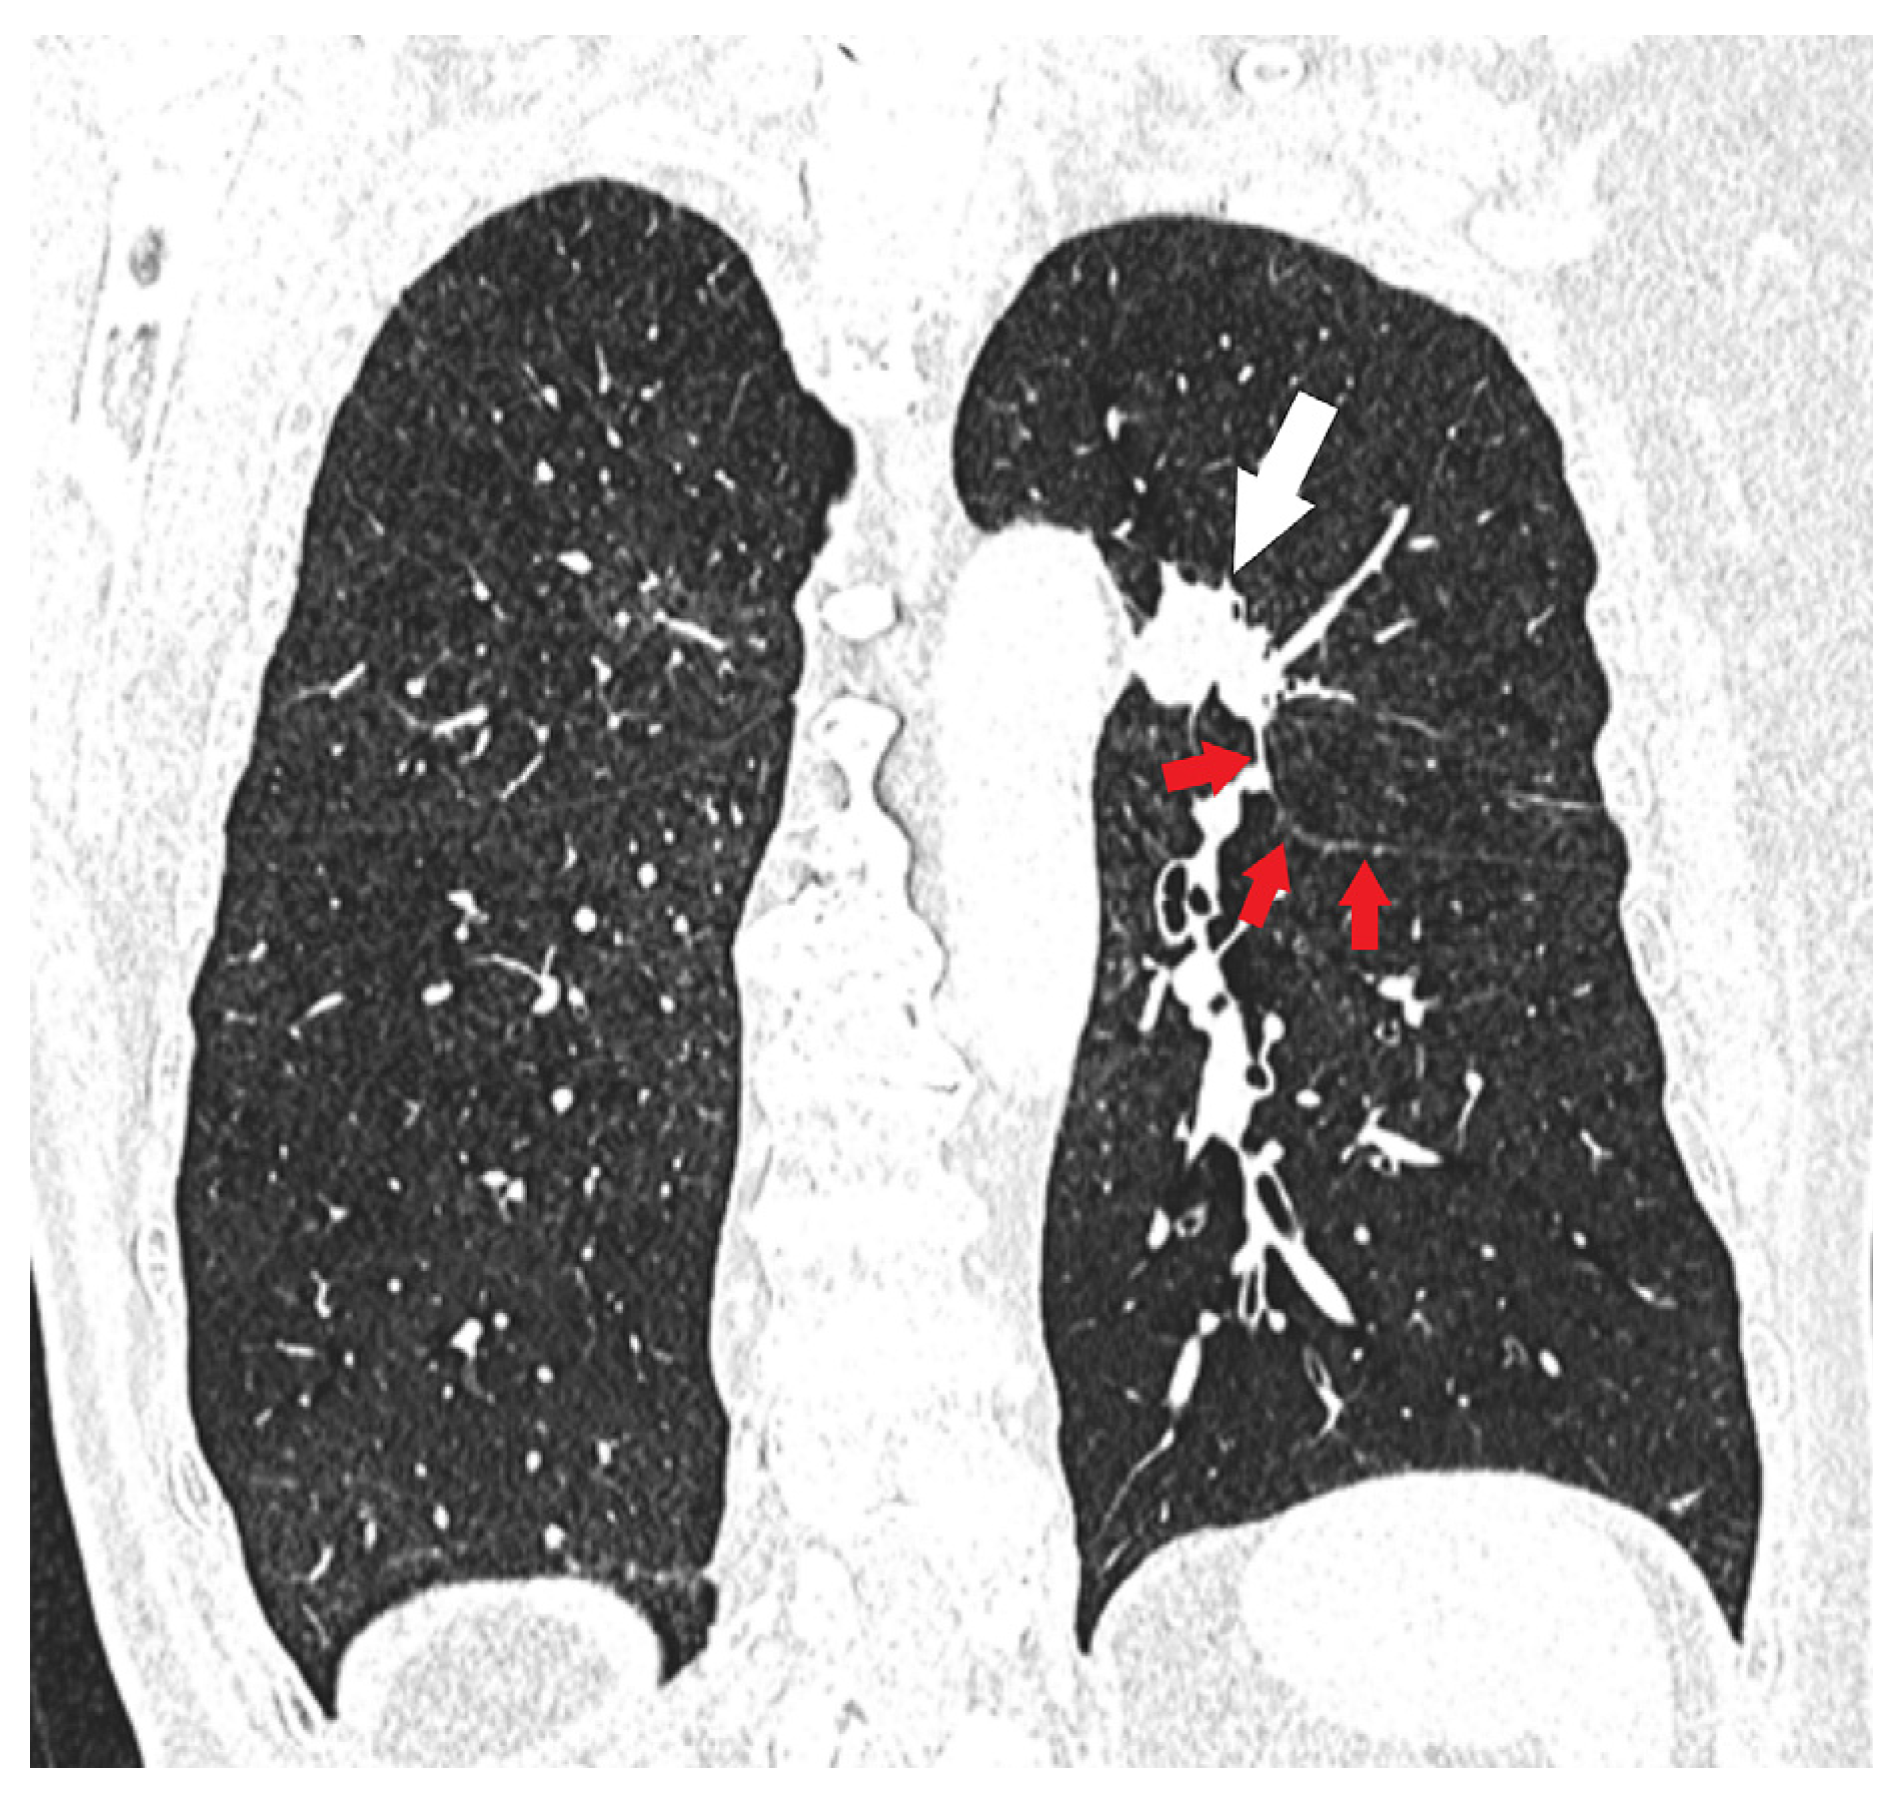

| T4 | Tumor > 7 cm in the greatest dimension Invasion of the mediastinum, thymus, trachea, carina, recurrent laryngeal nerve, vagus nerve, esophagus, or diaphragm Invasion of the heart, great vessels (aorta, superior or inferior vena cava, intrapericardial pulmonary arteries or veins), supra-aortic arteries, or brachiocephalic veins Invasion of subclavian vessels, vertebral body, lamina, spinal canal, cervical nerve roots, or brachial plexus Separate tumor nodule(s) in a different ipsilateral lobe than that of the primary | Signs of mediastinal invasion: infiltration of the mediastinal fat or structures that indicate the T4 stage, tumor–mediastinum contact length of more than 3 cm, an obtuse angle between the tumor and the mediastinum [37] Signs of vascular invasion: disappearance of the fat layer between the mass and the vessel, the angle between the mass and vessel wall >90°, a stenosis or deformation of the vascular lumen [41,42] |